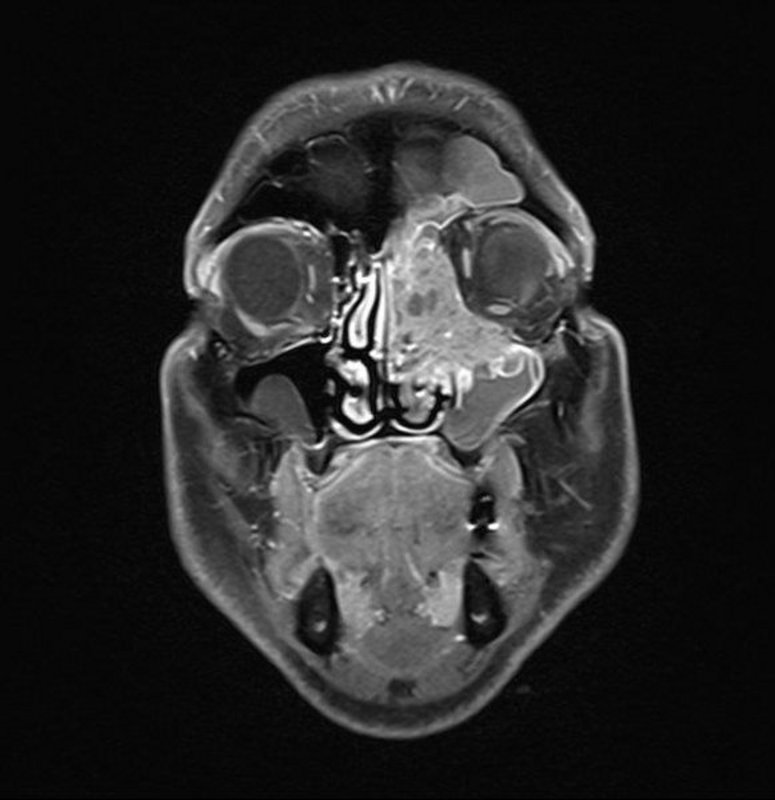

Bei den häufig sehr ausgedehnten Eingriffen am Gesichtsschädel, beispielsweise auch bei Tumoren, die die Schädelbasis erreicht oder überschritten haben (Bild 1), können später sichtbare Narben häufig vermieden werden: Der notwendige Hautschnitt wird in die behaarte Kopfhaut oder in die Schleimhaut des Mundvorhofes gelegt. Neben den onkologischen und funktionelle Prinzipien werden somit auch die ästhetischen Gesichtspunkte gewahrt.